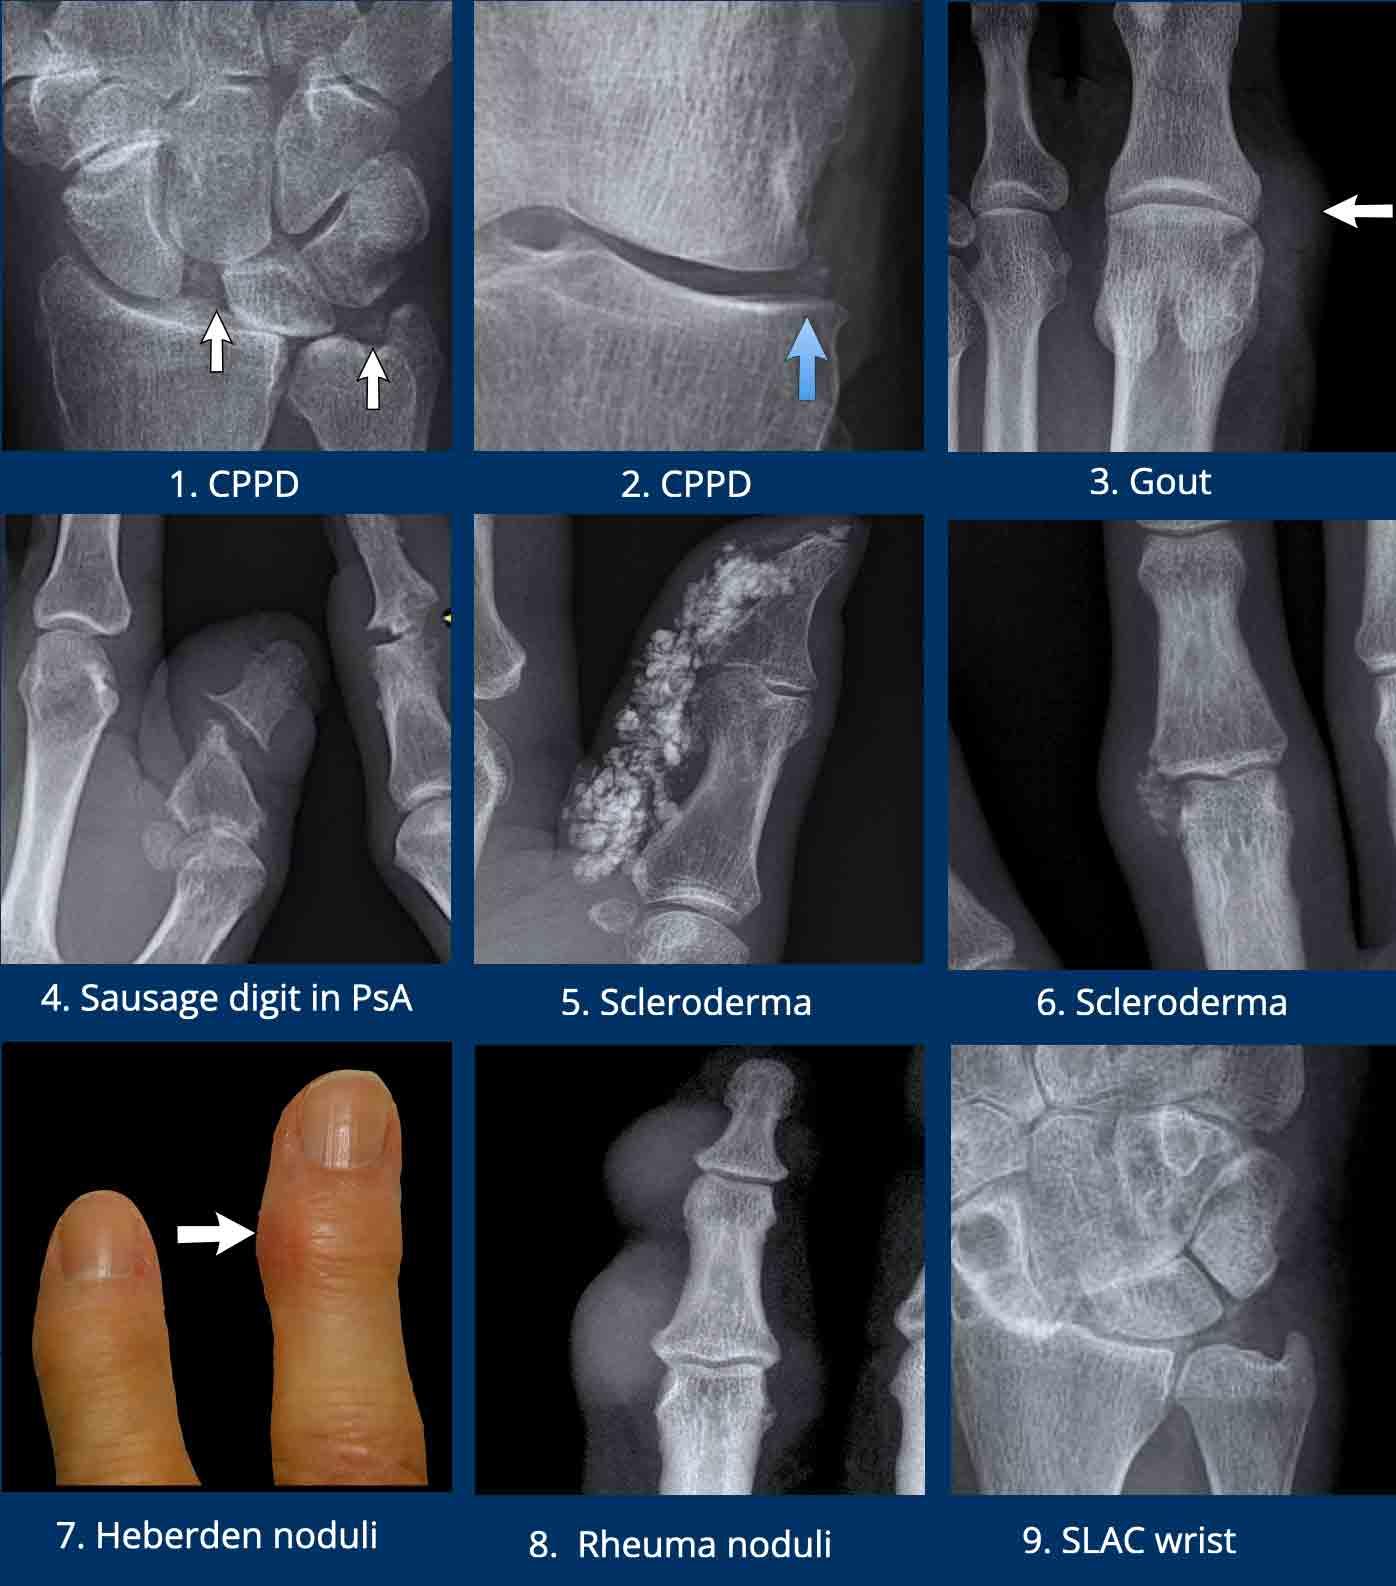

- Vôi hóa sụn (Chondrocalcinosis) là thuật ngữ mô tả các vôi hóa nhỏ trong khớp. Mặc dù không đặc hiệu cao, CPPD rất có khả năng khi vôi hóa sụn khu trú quanh TFCC, khớp quay-cổ tay hoặc trong khớp gối.

CPPD có thể gây phân ly SL (mũi tên trái). - Vôi hóa sụn trong khớp gối.

- Sưng mô mềm dạng nốt, hơi cản quang, cạnh khớp MTP1 gần như là dấu hiệu đặc trưng của bệnh gout. Các vị trí điển hình khác là các điểm bám gân quanh khớp gối, ví dụ gân khoeo, hoặc các gân gấp tại khớp cổ chân.

- Sưng mô mềm cạnh khớp dạng thoi là dấu hiệu thường gặp trong viêm khớp vảy nến và có thể ảnh hưởng toàn bộ ngón tay gây viêm ngón tay (dactylitis) hay “ngón xúc xích”. Lưu ý biến dạng bút chì trong cốc của khớp.

- Vôi hóa thô trong mô dưới da bao quanh đầu xa các ngón tay hoặc ngón chân rất có khả năng do xơ cứng bì.

- Xơ cứng bì

- Nốt Heberden, do gai xương trong viêm xương khớp

- Nốt thấp khớp. Các nốt mô mềm này quá lớn để là nốt Heberden và không có gai xương.

- Vôi hóa sụn trong CPPD. Một lần nữa, phân ly SL được ghi nhận, kèm thoái hóa thứ phát nặng. Tình trạng thoái hóa nặng này được gọi là cổ tay SLAC, viết tắt của Scaphoid Lunate Advanced Collapse (Xẹp tiến triển xương thuyền – xương nguyệt).